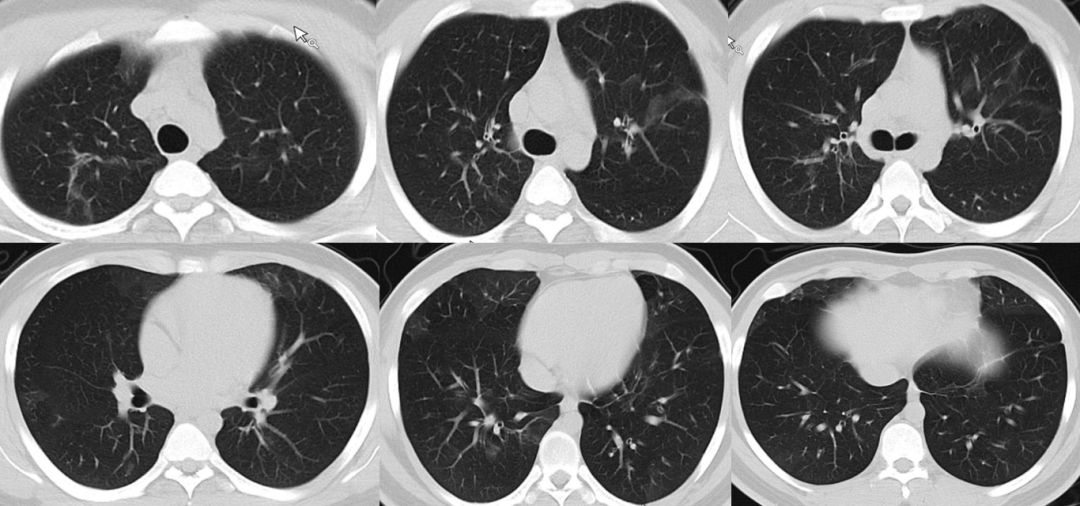

入院前影像学:患者2022年6月15日和11月25日胸部CT显示少量沿肺纹理分布的渗出,病变较轻(图1,图2)。2023年10月24日我院急诊胸部CT可见两肺广泛多发磨玻璃影(图3)

图3  2023年10月24日胸部CT